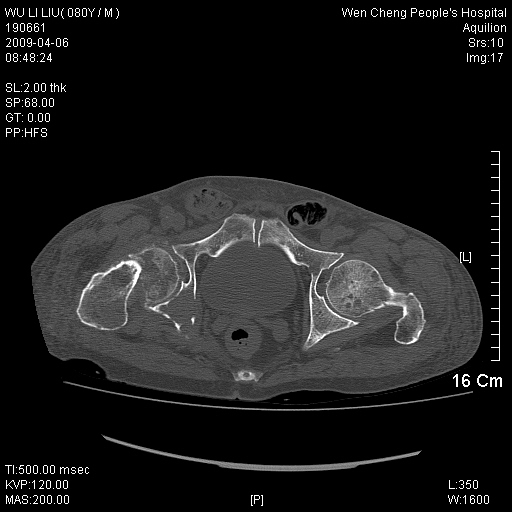

以下是引用zjzjr在2009-4-7 12:13:00的发言:[br]支持多发性转移瘤,右股骨颈骨折,腰椎亦有压缩性骨折.肝内胆管结石伴胆内外胆管扩张,左肾结石.

以下是引用liaoqiang在2009-4-7 8:44:00的发言:[br]考虑多发性骨髓瘤伴肝肺转移、肝内胆管结石、左肾结石、右股骨颈骨折。

以下是引用余辉在2009-4-7 8:52:00的发言:[br]椎骨及骨盆骨质疏松,骨破坏主要累及椎体,各骨破坏较广泛,各病灶边缘均较清晰锐利,血沉增快,白细胞增高.支持考虑多发骨髓瘤,建议查本尿周氏蛋白.[br]胆内胆管及左肾结石[br]右股骨颈骨折,考虑病理性